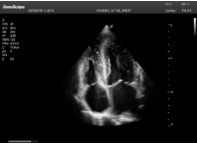

2相控陣探頭

探頭面是平面,接觸面小,近場(chǎng)視野最小,遠(yuǎn)場(chǎng)視野大,成像視野呈扇形,適用于心臟。

心臟探頭通常按應(yīng)用人群劃分為成人、兒童、新生兒三類:(1)成人心臟位置最深、搏動(dòng)速度慢;(2)新生兒心臟位置較淺、搏動(dòng)速度最快;(3)兒童心臟的情況介于新生兒與成人之間。

肥厚性心肌病-心尖四腔